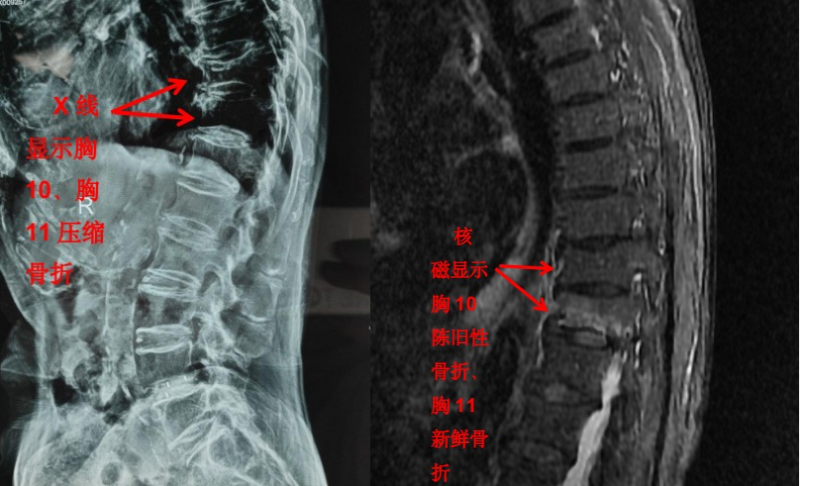

但是对于大部分软组织病变如椎间盘、椎管内神经、有没有占位性病变等却无能为力。如果患者有压缩骨折,X 光片也无法判断是新鲜骨折还是陈旧骨折,这样也就无法定制下一步诊疗计划。

随着科技进步及医学的发展,核磁已经是脊柱外科不可或缺的检查手段。对脊柱、韧带、椎间盘、椎管内神经及椎旁组织显影都优于 CT,通过腰椎核磁我们可以直观地看到椎间盘突出的程度、神经受压的程度,以及压缩骨折的新鲜程度。

核磁相对于 CT 和 X 线检查显像更清晰,内容更全面,那么所有腰背部疼痛的患者来就诊后都应该做核磁吗?答案当然是否定的。X 光、CT 和核磁这三种检查侧重点不同,在对疾病的诊治过程中都有着不可替代的作用。

核磁虽然显像更全面,但都是层扫,直观整体的信息欠缺,X 光片虽然内容少,但可以显示出脊柱整体的影像。几种检查互相补充,可以让疾病诊断更加明确。

前面提到的腰椎压缩骨折,X 光片可以看出楔形变,但无法判断新鲜骨折还是陈旧骨折,进一步完善腰椎 MRI 才能明确诊断,做出下一步治疗计划。